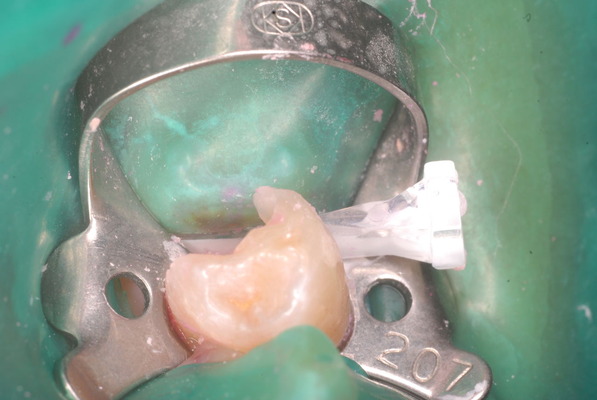

注射もせずに取れるだけ虫歯という病原菌を丁寧に除去し、消毒し、ぎりぎりのところで鎮静効果を持つセメントで被覆するのです。

まだ虫歯は残っていますが危険なので除去せずにそのまま消毒して鎮静セメントを挿入しました。

隣の歯との間をプラスチックで閉鎖し、唾液の侵入を防ぎました。でもまだ虫歯は残っています。

鎮静セメントを詰めて終了しました。後は神経の傷が治癒するのを待ちます。半年以上はかかります。